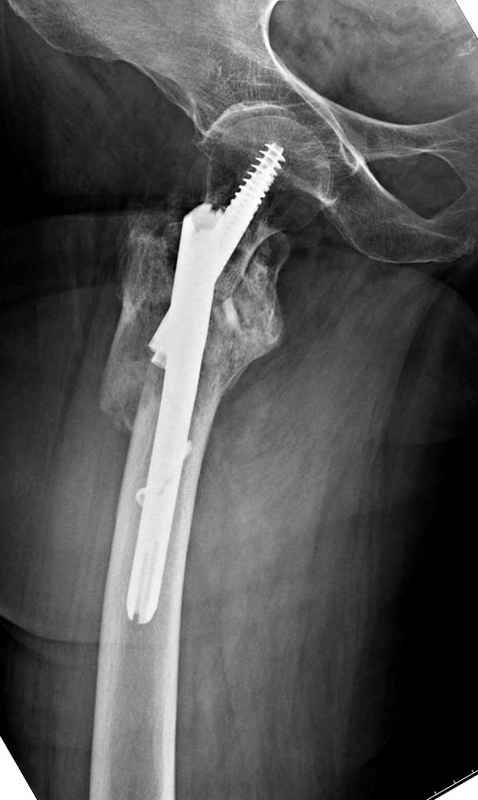

Здесь 83 года, травма в результате падения

Djoldas Kuldjanov, M.D.

Department of Orthopedic Surgery

St. Louis University